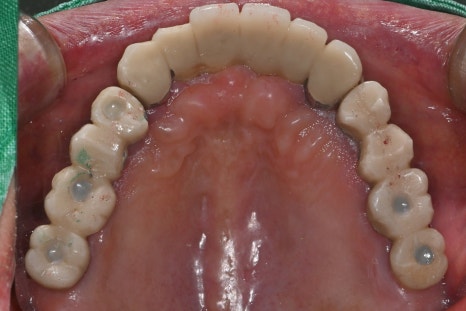

왼쪽 사진: 윗니 보철은 전체적으로 고정성이 좋고 교합이 안정적으로 설계되었습니다.

왼쪽 사진: 윗니는 대부분 임플란트 보철이지만 나사홀이 오픈되어 보완이 필요한 상태였습니다.